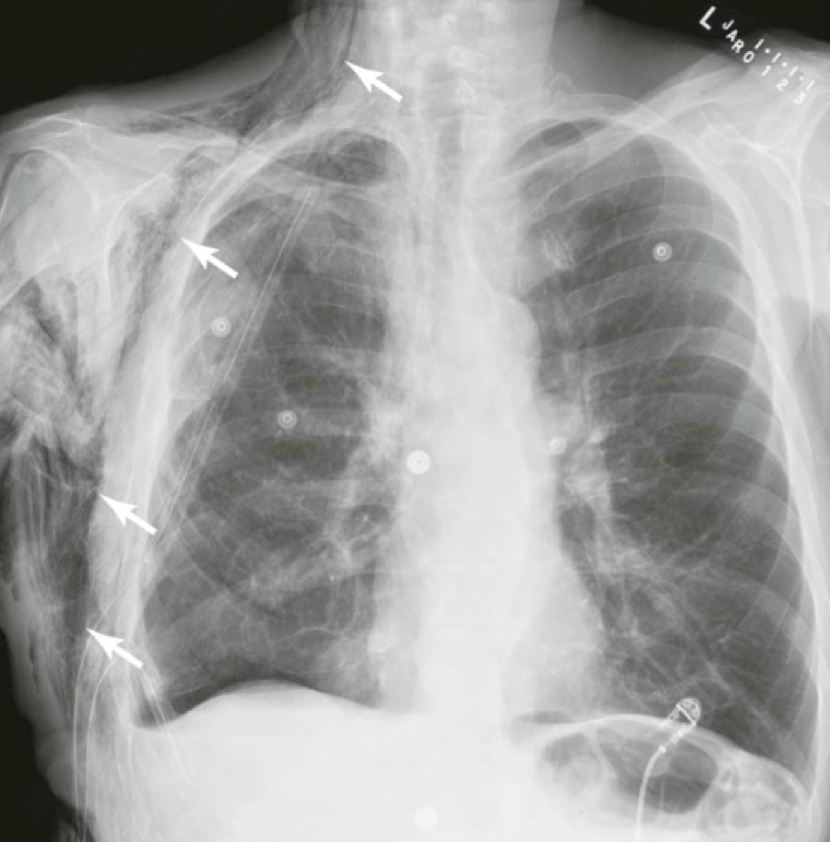

Question 26

Question

What does this image show?

Answer

• Pneumomediastinum

• Pleural Effusion

• Subcutaneous Emphysema

• Hydropneumothorax